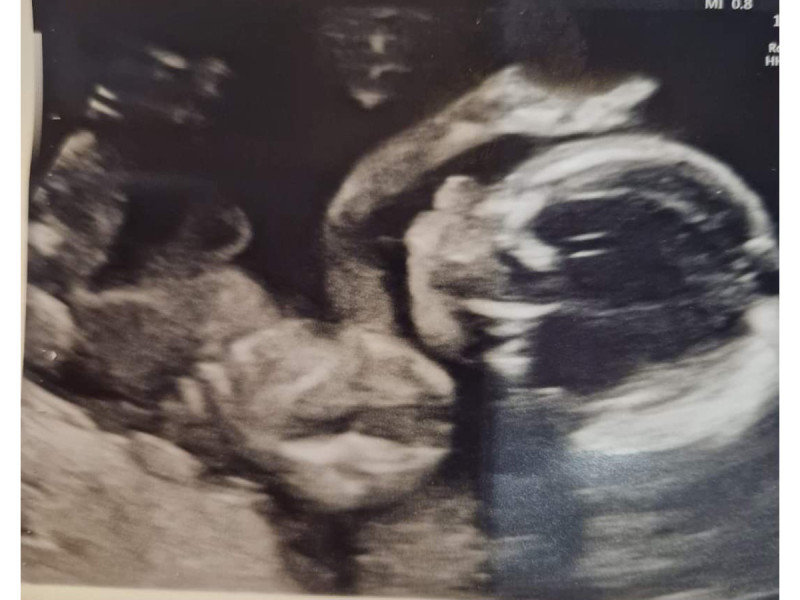

My husband and I knew we would have a challenging few weeks ahead of us. The following week, I then attended my local maternity unit where an ultrasound was carried out and worked out a date for the CVS testing. Going for our first ultrasound, my husband and I were very nervous. After the ultrasound, the midwife contacted genetics with all the relevant information. Five weeks passed and I was seen at the Foetal Medicine Unit in Glasgow, after a quick ultrasound I was told I was 11 weeks and 2 days pregnant. I was extremely nervous that day but the team was fantastic and supported me every step of the way.

The team then explained the procedure and got me to sign a consent form to say I was happy to go ahead. There was a small risk of infection and miscarriage. I then lay on the bed holding my husband's hand as I was terrified by this point, unsure what I was going to experience. A small injection of local anaesthetic was put in my stomach. Once this worked, a large needle then went through the stomach and cells were then taken from the placenta. This was slightly uncomfortable and painful. The other doctor then took a small sample and placed it under the microscope to ensure enough cells were collected and could be sent away to the lab for testing. I then had to wait in a room for 30 minutes, to ensure I was ok and did not have any effects. For 2 days afterwards, I had bad cramping and was advised to take a few days off work to let things settle.